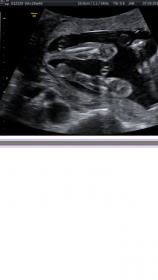

Any idea what i am looking at? I thought legs? Does this help with gender? Thank you :)

Thanks Eighme! I just wasnt sure if maybe the little dot in the middle was gender related?

That dot in the middle could be anything. Hand, Cord, gender. There is no way to tell from this pic.